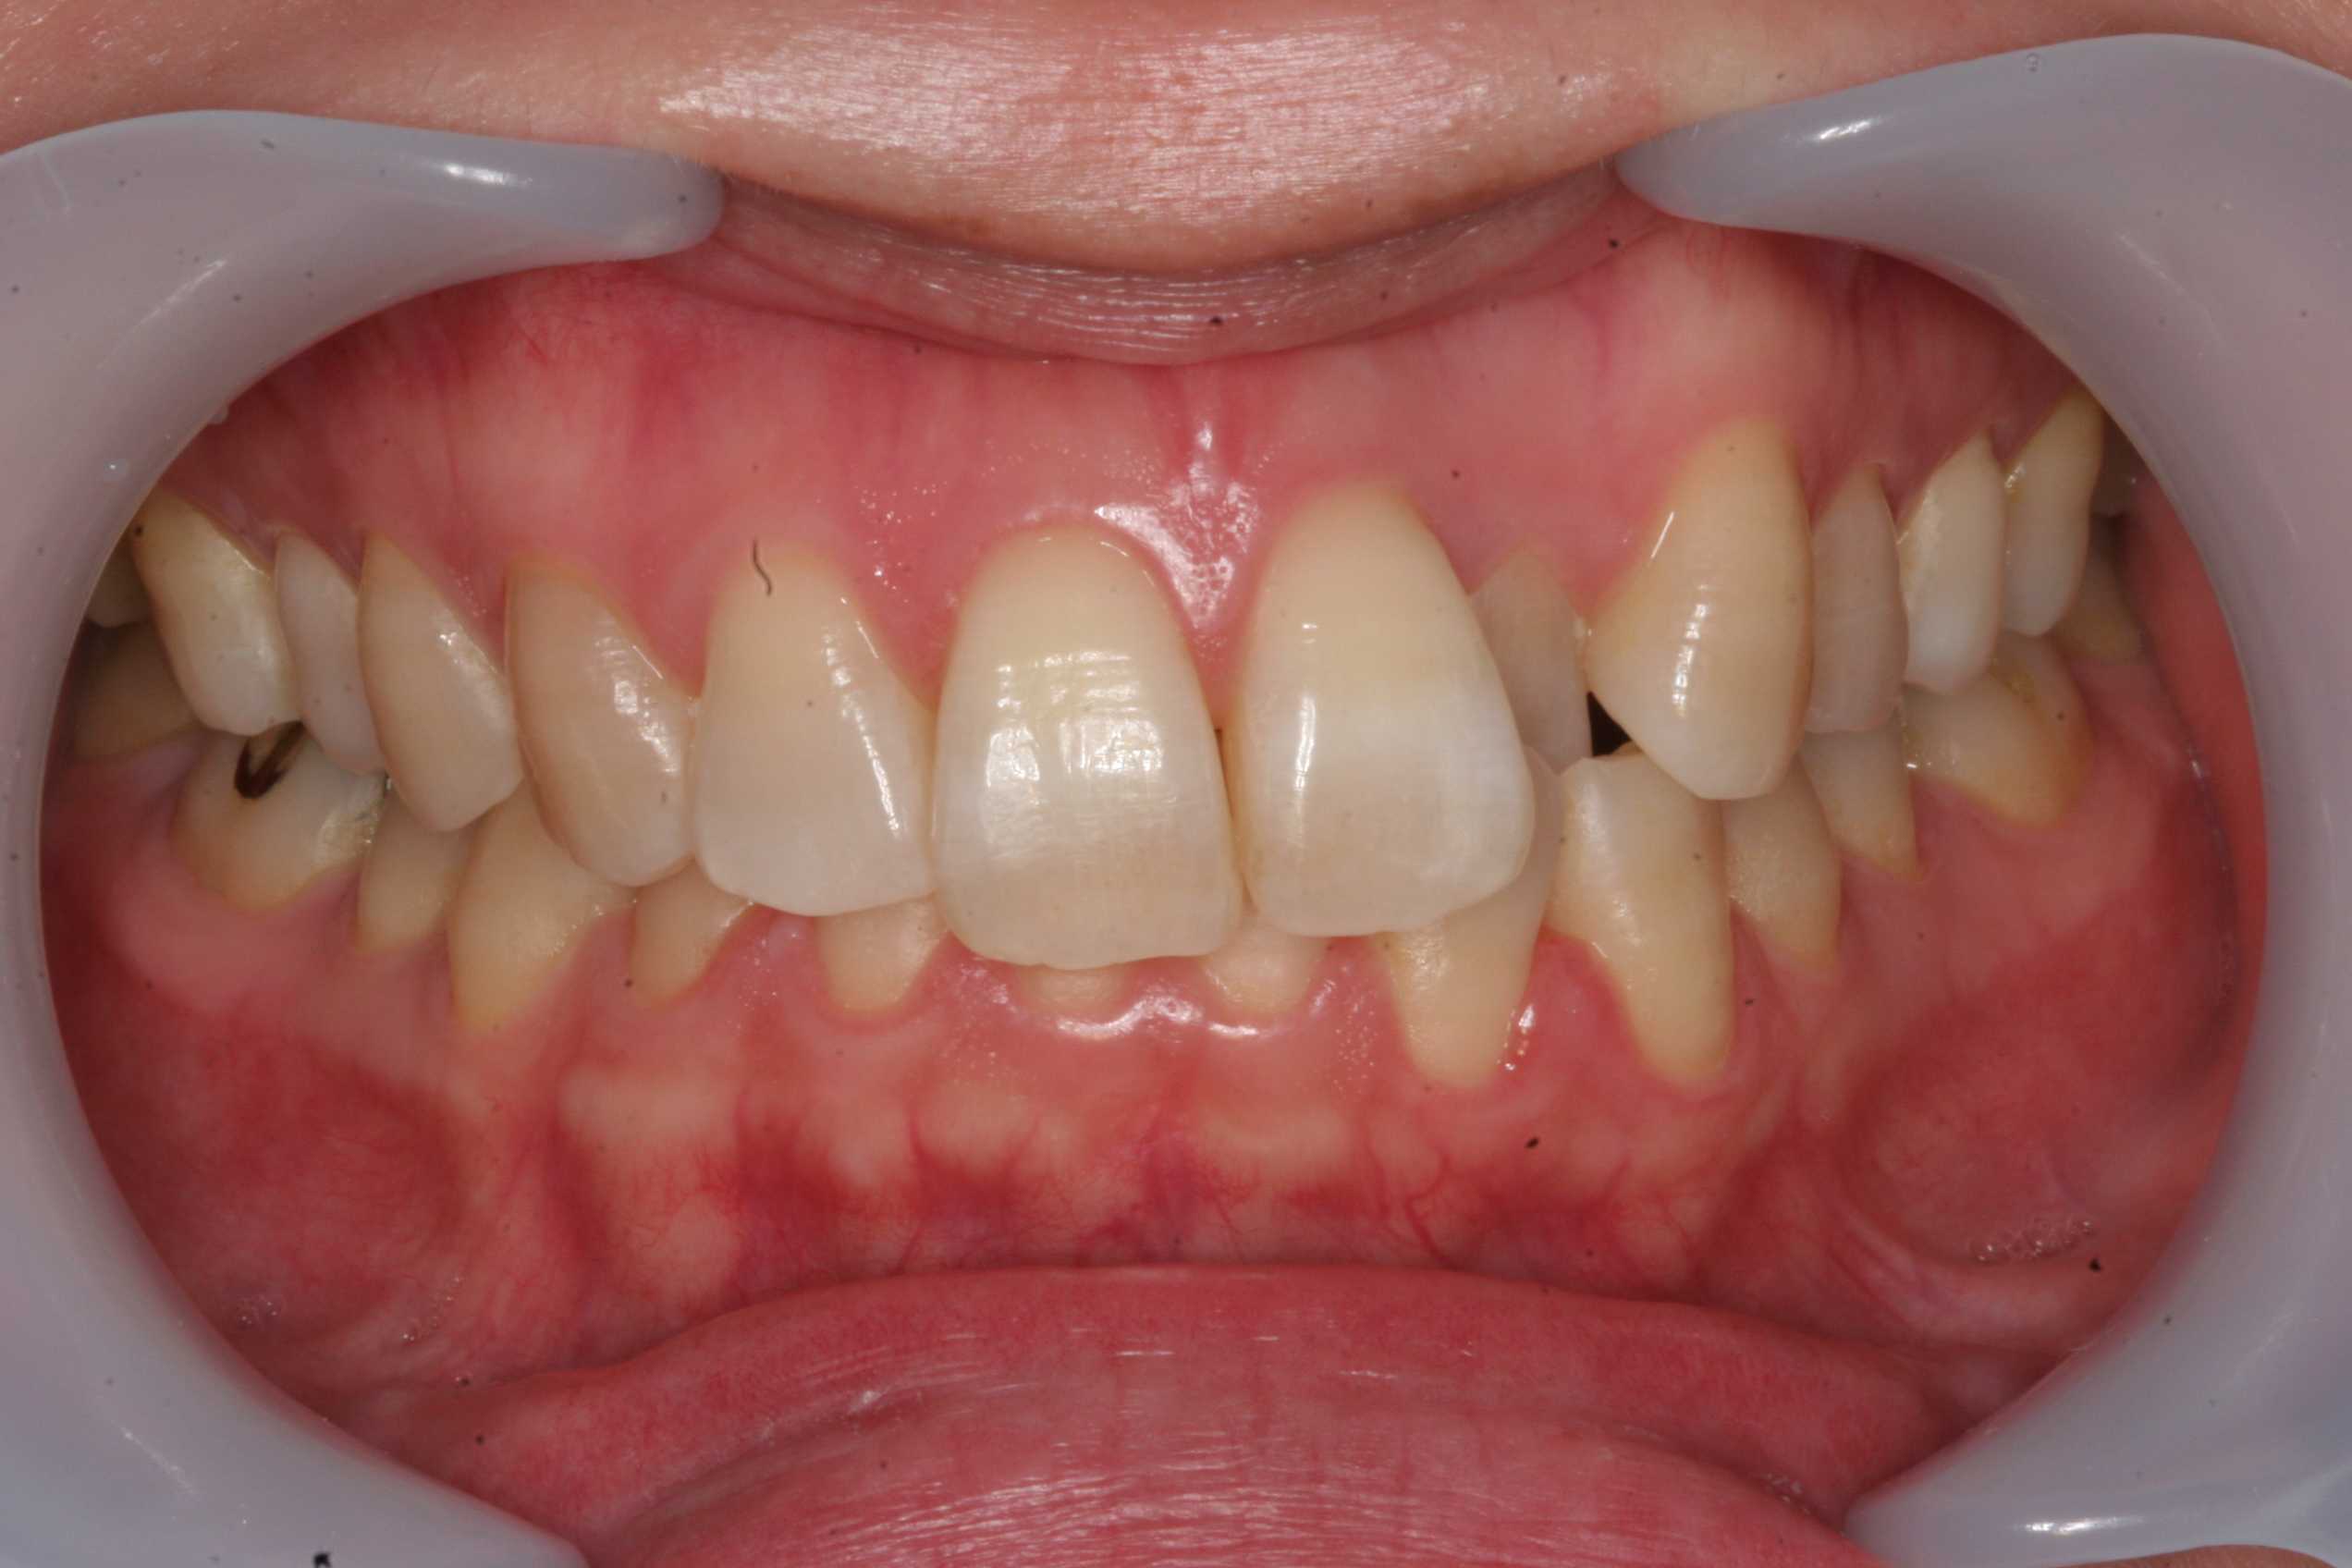

40代女性、左上2、クロスバイト子供の頃から気にしていて、コンプレックスに悩まされていたらしい。この方のお姉さんに聞いて初めて知った。矯正をしたいと依頼があったので、歯列を広げることから始めたのだが、僕はあまり気にしていなかったので、しばらく忘れて放置していた。その話を聞いて本格的に始めた経緯がある。前回のつづきhttps://plaza.rakuten.co.jp/mabo400dc/diary/202509250000/今年になってバタバタとブラケット装着して歯列矯正を始めた印象があるのだが、画像を調べてみると2016年から始めていた。真面目に四六時中上下の拡大装置を装着していただいて、1年後の2017年にはかなり歯列が拡大した。その後僕が忘れていて、2023年から治療を再開した。今日はそこまで。2016/02/292017/04/10かなり開いているのが見えると思う。この間ブランク、拡大装置の装着はしていただいていた。拡大装置の再作成。もう少し歯列拡大することにした。2023/05/242025/04/01ブラケット&ワイヤーを装着して2番の被蓋を改善するには歯列をもっと広げてスペースを作るしかない。もしくは抜歯してスペースを作るのだが、それはしたくない。歯列を広げるには真面目に拡大装置を装着しても2年かかる。次回はブラケットの選択などブラケット&ワイヤーの基本から。歯学部を出ただけでは全く分からない。歯科矯正学の大学院に進学したり医局に入ってご奉公するしかない。それも人気が高く入れてもらえない。セミナーに参加すると数十万円かかる。ここでは無料公開だwつづく

40代女性、左上2、クロスバイト子供の頃から気にしていて、コンプレックスに悩まされていたらしい。この方のお姉さんに聞いて初めて知った。矯正をしたいと依頼があったので、歯列を広げることから始めたのだが、僕はあまり気にしていなかったので、しばらく忘れて放置していた。その話を聞いて本格的に始めた経緯がある。最近はマウスピース矯正が流行って、こういう症例も矯正専門医でなくても治療を提供できることが視野に入って来ている。しかし、元々歯列が狭い症例で、非抜歯でするには初めに歯列を広げる処置をしなくてはならないのだが、歯列が狭くなる根本原因は実はあまり知られていないというか、矯正専門医も気にしていないフシがある。この歯列が狭くなる根本原因は横向き寝、うつ伏せ寝、頬杖等の態癖と呼ばれる顎に加わる外力によるものだ。例え歯列矯正が終わったとしても態癖が治らないとまた元に戻ってしまう。この態癖対策が難しい。ここでご紹介している部分矯正をマスターすれば矯正専門医でなくても非抜歯でこのような症例に対応できるので患者の信頼度は増すと思う。是非取り入れていただきたい。とりあえずbefore/after から。歯列が広がってきていることが分かると思う。beforeafterつづく